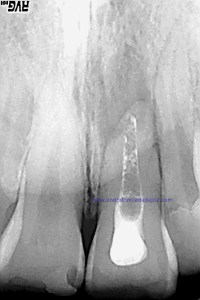

Colocamos la barrera apical verificando que conseguíamos un buen sellado:

(Rx Mesioradial)                                                               (Rx Ortoradial)

Una vez que hemos transportado y barrera apical, hacemos el backfilling con la Pistola Obtura II.